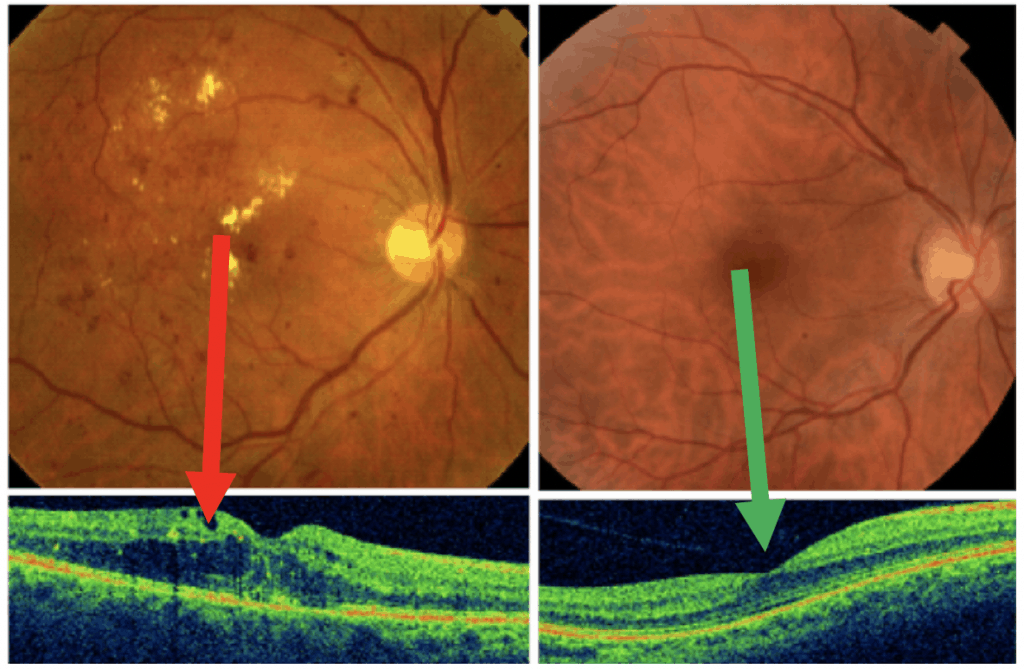

DIABETIC MACULAR EDEMA (DME)

What is macular edema?

- It is the build-up of fluid in the macula, an area in the center of the retina.

- The macula is the part of the retina responsible for sharp, straight-ahead vision.

- Fluid build-up causes the macula to swell and thicken, which distorts vision.

What causes macular edema?

- In diabetes, high blood sugar affects the small blood vessels or microcirculation

- The retinal blood vessels are some of the smallest blood vessels are often affected first in diabetes.

- Abnormal leakage and accumulation of fluid in the macula occurs from these damaged blood retinal vessels.